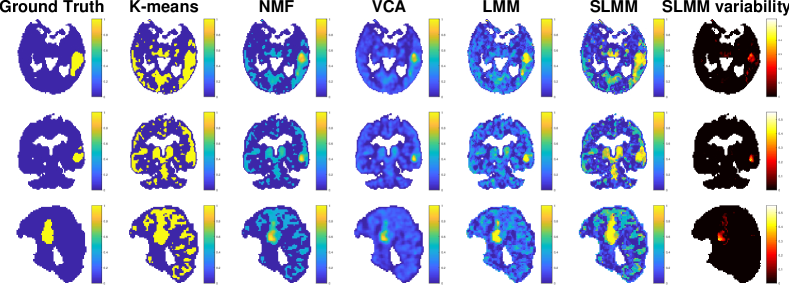

Refer to caption

Figure 7: factor proportion maps of the real PET image with [F18superscript𝐹18{}^{18}F]DPA-714 of a subject with a stroke. The first 3 lines show a transaxial view while the last one shows a sagittal view. From top to bottom: the specific gray matter, white matter, non-specific gray matter and blood.

Figure 7 depicts the factor proportion maps estimated by the compared methods. The corresponding estimated factor TACs are shown in Fig. 8. The LMM and SLMM algorithms estimate four distinct TACs associated with different tissues, as expected. In the first row of Fig. 7, corresponding to SBF, all methods seem to correctly recover the main localization of the stroke area. However, the proposed SLMM approach identifies a significantly larger area. This result seems to be in better agreement with the stroke area identified in the MRI acquisition of the same patient (see 111st column of Fig. 9). Moreover, the specific gray matter factor proportion maps estimated by SLMM and K-means shows high values in the thalamus, which is a region known to present specific binding of [18F]DPA-714. Another remarkable result is the factor proportion maps for the blood. The sagittal view represented in the last row is in the exact center of the brain. Both NMF and SLMM recovers factor proportion maps that are in very good agreement with the superior sagittal sinus vein that passes on the higher part of the brain. On the contrary, VCA estimates two factors which seem to be mixtures of the vein TACs and other region TACs.

Fig. 9 depicts three different views of the AVC area identified by the expert on MRI acquisition (111st column), the estimated specific gray matter factor proportions (222nd-666th columns) and the estimated corresponding variability (777th column). This figure shows that SLMM provides sharper and more accurate maps, characterized by a larger area with high uptake, as in the MRI ground-truth. This figure also compares the map recovered by K-means, which is used as the initialization of the proposed SLMM, with the final SLMM estimate. It is possible to note an interesting improvement of the final estimate when compared to its initialization. This demonstrates that the method converges to an estimation of the specifically bound gray matter that is more accurate with the proposed model.

Figure 9: From left to right: MRI ground-truth of the AVC area, SBF coefficient maps estimated by K-means, NMF, VCA, LMM, SLMM and SBF variability estimated by SLMM.